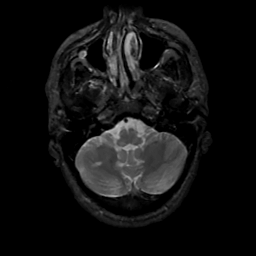

MR Study #3, February 24, 1991 -- Slice #9

[Home][Help][Clinical][Tour 1][Tour 2] Slice 9